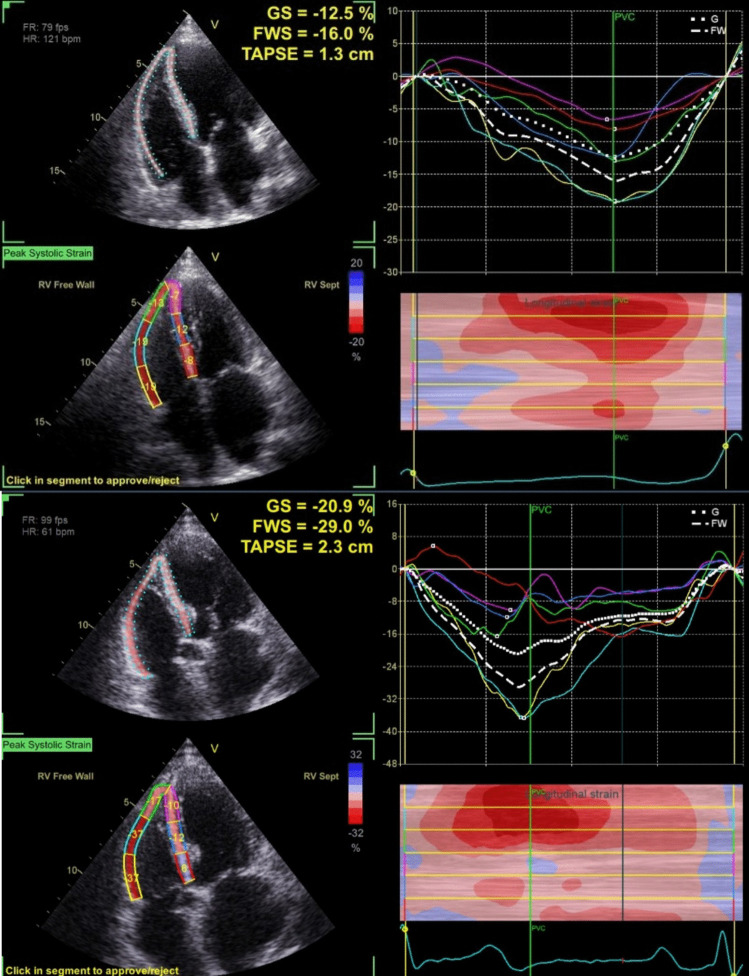

Method: Basic and speckle-tracking echocardiography has been performed on 42 individuals with symptomatic idiopathic outflow tract PVC before and 1 month after a successful ablation.

Result: At the baseline of the study, there were 26 patients with RV subclinical dysfunction and 16 patients without RV dysfunction. Patients with RV subclinical dysfunction exhibited significantly higher PVC burden and QRS complex duration than those with normal RV function (p < 0.05). A PVC burden ≥ 21% (OR 9.11, 1.54-53.87, p = 0.015) and a QRS complex duration ≥ 138 ms (OR 5.74, 1.07-30.90, p = 0.042) were independently associated with RV subclinical dysfunction. In both groups, measurements of RV subclinical function before and after ablation, specifically by free wall longitudinal strain (FWLS) and global longitudinal strain (GLS), demonstrated significant changes. These improvements were more pronounced in the group with RV dysfunction (FWLS 9.7 ± 4.0, p < 0.001; GLS 7.5 ± 4.2, p < 0.001). Lower initial FWLS and GLS before ablation emerged as significant parameters in the multivariate analysis for the improvement of RV function post-ablation.

Abstract Image